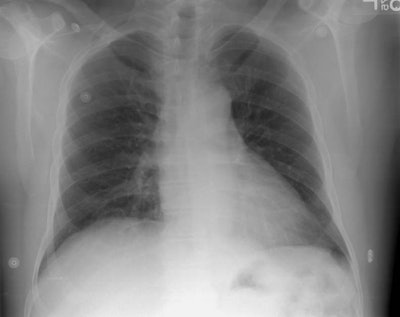

The patient shown in the case below is a 55 year old man who presented with left sided pleuritic chest pain. The radiograph demonstrated a rounded density over the medial aspect of the left hemidiaphragm (not well seen on the lateral view). A previous chest radiograph 4 months earlier did not demonstrate this abnormality. The patient had no signs of infection, and a smoking history. A CT of the chest was performed to evaluate this finding.